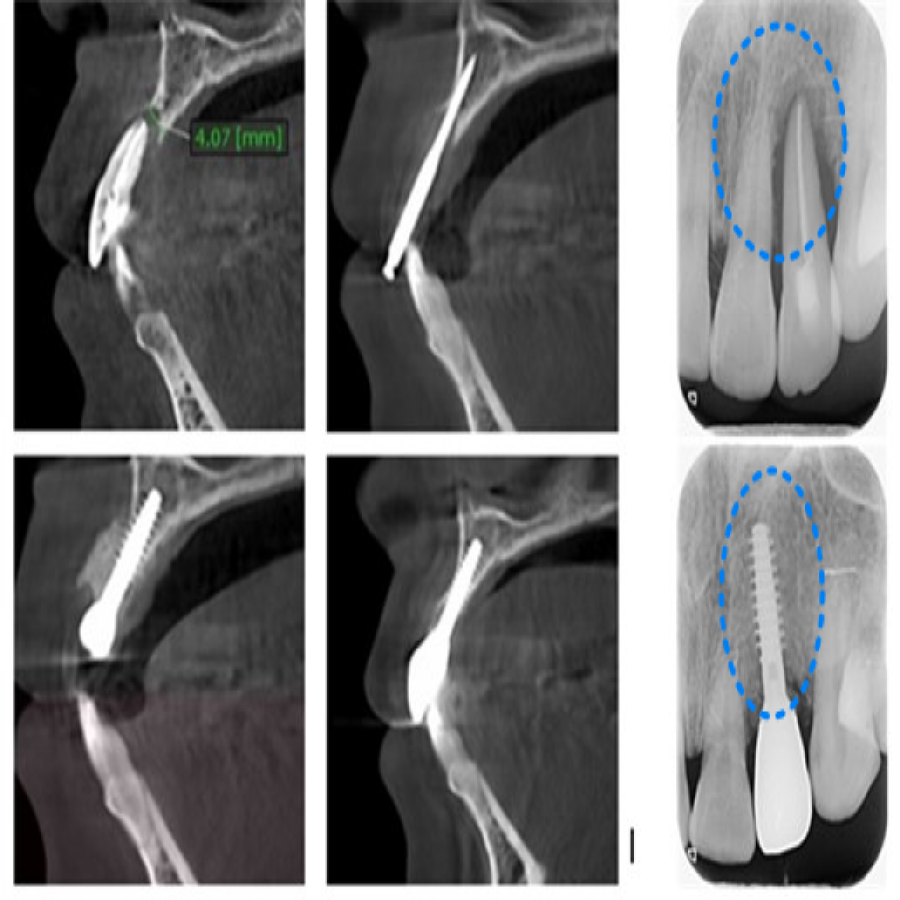

상기 환자분은 잇몸뼈가 많이 흡수되어 있었습니다. 일반적인 임플란트 식립법으로는 심하게 녹은 치조골 재생을 위해 발치 후 잇몸이 다 아물 때까지 기다린 후에 수술이 이루어져야 합니다.

이때 아문 잇몸을 절개한 후 뼈 이식과 다른 보조 재료도 함께 사용하기 때문에 잇몸을 늘리는 과정이 필연적이며, 그렇게 되면 수술 후에도 많은 통증과 붓기가 따를 수밖에 없습니다. 본원에서는 환자분의 불편함을 줄여드리고 만족도를 높이기 위해 최소침습으로 앞니 임플란트를 진행했습니다.

매직코어 임플란트는 지대주와 인공치근 부분이 일체형으로 형성되어 치조골 폭이 좁거나 상태가 좋지 않은 경우에도 골이식이나 골성형을 최소화하여 식립할 수 있는 최소침습용 임플란트 입니다. 매직코어는 식립 시 나사선 사이의 Interthread bone이 손상되지 않아 골 회복에 유리하고 최소침습으로 일반 임플란트 보다 골 유착이 유리합니다.

본원에서는 3D CT와 MEDIT i500, MDEITi700 구강 스캐너를 활용하여 환자분의 치조골 상태 및 안면 골격, 턱관절 및 해부학적 구조물의 위치 등을 정밀하게 파악 후 치료를 진행하고 있습니다.